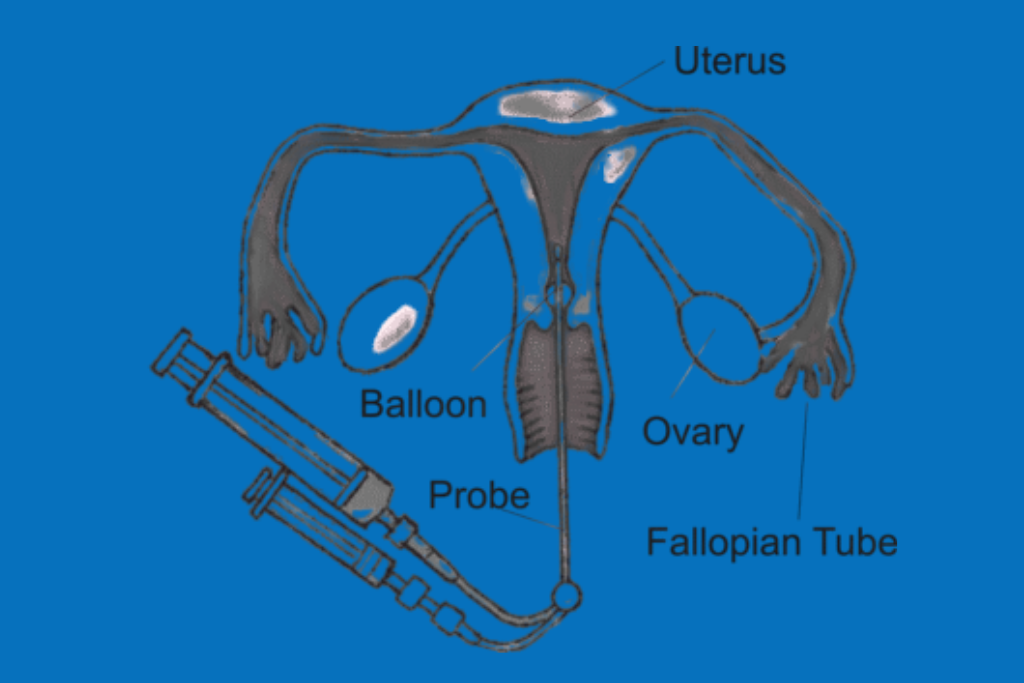

HyCoSy (Hysterosalpingo-Contrast Sonography)

An ultrasound technique using contrast fluid to check if fallopian tubes are open.

Why are HyCoSy and SIS tests recommended?

These tests help in identifying fallopian tube blockages and uterine abnormalities, which are common causes of infertility, allowing better treatment planning.